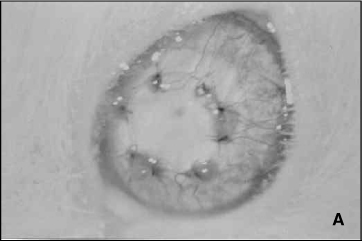

A figura 6A é um exemplo de enxerto corneano considerado não rejeitado, classificado clinicamente como apresentando opacidade igual a 0, edema igual a 1, neovascularização igual a 2. Trata-se de animal pertencente ao grupo T 7 no 17º pós-operatório. A Figura 6B é um exemplo de enxerto corneano considerado rejeitado, classificado clinicamente como apresentando opacidade igual a 4, edema igual a 2, neovascularização igual a 3. Trata-se de animal pertencente ao grupo controle no 27º dia pós-operatório.